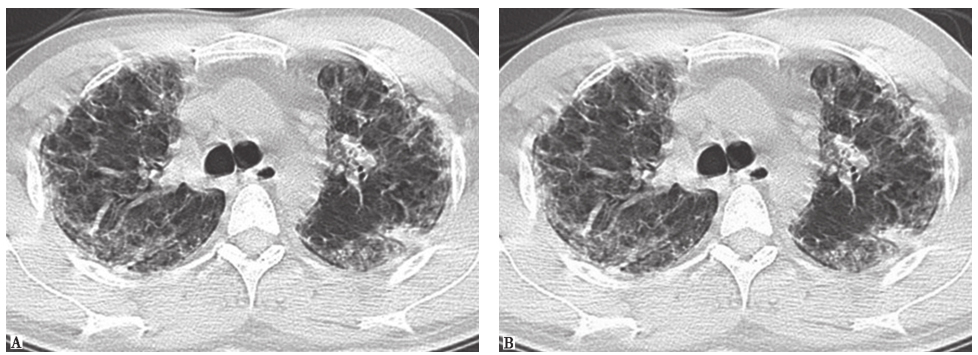

3)呼吸性细支气管炎伴间质性肺疾病(RB-ILD):最常见的CT表现是中央支气管和周围支气管管壁增厚,其他CT表现包括小叶中央小结节影、磨玻璃影和伴有气体潴留的肺气肿(图7)。患者应有相应的临床背景资料(尤其是在最近6个月内有吸烟史),有相应的临床和影像学表现,肺活检符合RB-ILD表现,同时排除其他更为严重的弥漫性间质性肺疾病。本例患者有吸烟史,CT可见小结节影、磨玻璃影,因此须进行相关检查以与RB-ILD相鉴别。

图7 RB-ILD胸部CT表现

男性患者,41岁,胸腔镜肺活检病理证实为呼吸性细支气管炎伴间质性肺疾病。CT示两肺弥漫分布小叶中心型小结节影、周围支气管管壁增厚

铁尘肺:是由于肺内巨噬细胞积聚三氧化二铁颗粒形成的,通常是吸入过多焊工烟雾造成的,故也称为焊工尘肺。绝大部分铁尘肺不引起肺纤维化和肺功能损害,可以无任何临床症状而在体检时发现。胸部CT可以发现双肺多发性边界不清的小叶中心型小结节影,少部分患者可发现线状影、斑片状实变影和广泛磨玻璃影(图11)。铁尘肺的诊断主要依据职业接触史和影像学特征,少数患者需要肺活检病理证实。本例患者自诉其接触金属粉尘可能主要为铁粉尘,但CT所示小结节影不如典型铁尘肺分布广泛,且临床症状相较于铁尘肺偏重,最终仍需病理结果来明确鉴别。

巨细胞间质性肺炎(giant cell interstitial pneumonia,GIP):是暴露于含有钴、碳化钨等硬金属及其化合物引起的少见职业相关性间质性肺疾病。其典型胸部CT表现为弥漫性磨玻璃影、小结节影、广泛网状影和牵拉性支气管扩张改变,以及大小不等的实变影(图12)。晚期患者可见肺部广泛的结构扭曲和蜂窝样改变。GIP最终诊断应该根据职业接触史、影像学特征和病理学等证据。本例患者从事钻孔工作8年,接触金属粉尘较多,有职业接触史,影像学特征也较符合GIP,但仍需获得病理学检查结果以明确诊断。

图11尘肺胸部CT表现

男性患者,42岁,经支气管肺活检病理证实为铁尘肺。胸部CT示两肺弥漫性磨玻璃样小结节影

图12巨细胞间质性肺炎胸部影像学表现

男性患者,32岁,从事刀具磨制工作9年,经支气管肺活检病理证实为巨细胞间质性肺炎。CT示两肺散在磨玻璃影、小结节影、小片实变影、牵拉性支气管扩张